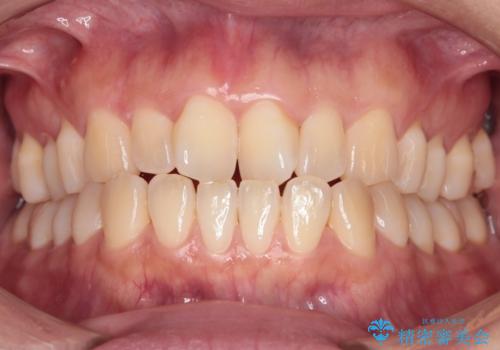

[ セラミック治療 ] 前歯の見た目を改善したい

担当医 大元洋佑